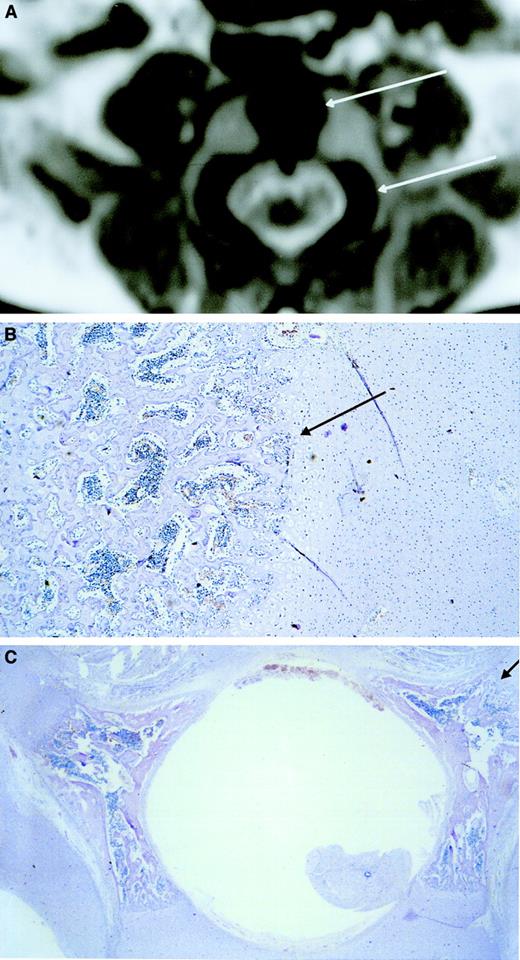

Ossification center.

MRI shows low signal intensity (black) in the central area of the vertebral body corresponding to an ossification center (upper arrow). Low signal intensity corresponding to an ossification center is also visible in the lateral area of the vertebral pedicles (lower arrow) (A). Microscopic transversal sections (4 μm) stained with hematoxylin-eosin of the central area of the vertebral body (B) and the lateral areas of the vertebral pedicles (C) show hematopoietic cells between the spiculae, indicating that the low-intensity areas visualized by MRI are hematopoietic areas. The upper and lower arrows in panel A correspond with the arrows in panels B and C, respectively. Original magnification × 40.